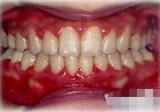

反対咬合(受け口)症例

初診時年齢24歳6ヶ月。前歯部反対咬合を主訴に来院。

骨格性反対咬合と診断し、外科的処置を併用して治療。

治療前 治療後

正面 正面 正面